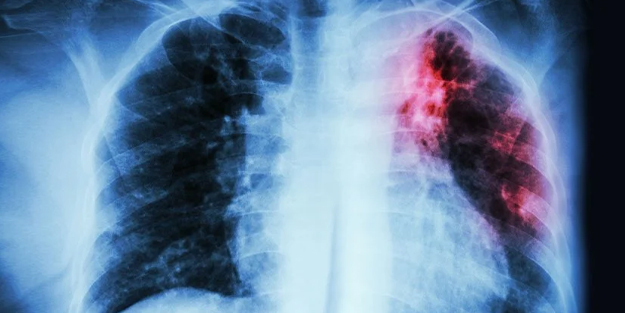

Avrupalı araştırmacılar yapay tatlandırıcılar ve kanser arasında bir bağlantı buldu. Fransız Ulusal Sağlık Enstitüsü'nden uzmanlar yapay tatlandırıcılarla ilgili yaptığı çalışmayı tamamladı. Çalışma, meme ve obezite ile ilişkili kanser riskini artırdığını buldu.

Büyük bir araştırma, diyet ve alkolsüz içeceklerde yaygın olarak kullanılan yapay tatlandırıcıların kanser riskini artırabileceğini iddia ediyor. Fransız Ulusal Sağlık ve Tıbbi Araştırma Enstitüsü ve Sorbonne Paris Nord Üniversitesi'nden uzmanlar, sekiz yıl boyunca 100.000 kişinin yemek programını ve sağlığını izledi. Düzenli olarak yapay tatlandırıcılar tüketen kişilerde kanser riskinde yüzde 13'lük bir artış buldular. Dana önce yapılan çalışmalarda böyle bir bulguya rastlanmamıştı.

Katılımcıların yaklaşık yüzde 37'si günde en az bir kez yapay tatlandırıcılar tüketti. Çalışmanın sonunda 3.358'ine kanser teşhisi konmuştu ve hastalıklarının tespit edildiği andaki ortalama yaşları 59,5 idi.

Bunlardan 982'si meme kanseri, 403'ü prostat kanseri ve 2.032'si obezite ile ilişkili kanserlerdi.